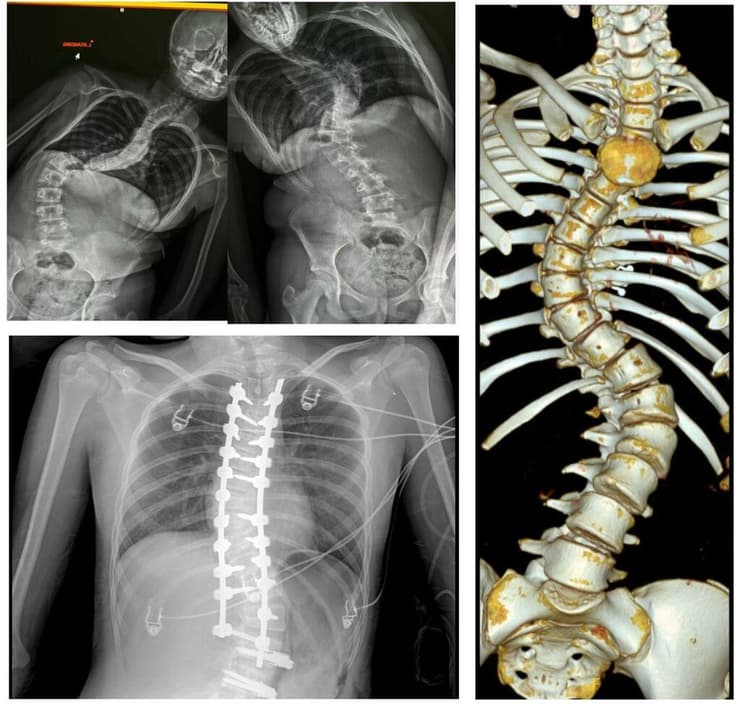

עם זאת, בשנים האחרונות מתפתחת גישה ניתוחית נוספת, שמבקשת להתמודד עם העקמת מבלי לשלם את המחיר של קיבוע מלא ואובדן תנועה – ניתוח משמר תנועה מסוג VBT – (Vertebral Body Tethering) המבוצע למתבגרות בשלב מוקדם של הגדילה ועקמת קלה יותר או ASC (Anterior Scoliosis Correction) - ניתוח משמר תנועה למתבגרות בשלב מאוחר יותר של הגדילה או עם עקמת גדולה יותר.

"הקיבועים הקלאסיים קיימים משנות השישים-שבעים, לעומת זאת הניתוחים מסוג VBT/ASC קיימים כ-15 שנה", מציין ד"ר ברבלק, "במסגרתם אנחנו מכניסים ברגים לחוליות בגב לא בגישה אחורית כמו במקרה הקלאסי, אלא מהצד דרך בית החזה במרווח הבין-צלעי ולאחר דפלציה של הריאה בצד שבו אנו נכנסים. לאחר מכן, להבדיל מהשיטה הקלאסית שבה מוחדר מוט קשיח לראשי הברגים אנחנו מניחים כבל גמיש ונועלים אותו לראשי הברגים בין החוליות. הכבל שומר על הגמישות המלאה של הגב ולכן ואין שום איחוי חוליות של הגב".

העיקרון הביומכני פשוט, אך אפקטיבי. לדבריו של ד"ר ברבלק, ביצוע ניתוח VBT מאפשר לתקן את העקמת עם השנים בתנאי שיש עדיין פוטנציאל גדילה. "תדמיין קערה קעורה שאתה שם על החלק הקעור שלה את הברגים – כשהילדה גדלה, הצד שלא מקובע ממשיך לגדול, והצד שמקובע נשאר באותו אורך - כך העקמת מתקנת את עצמה בנוסף לתיקון המבוצע בניתוח". גם כאן, העיתוי משחק תפקיד מרכזי. "ככל שאנחנו מבינים בשלב יותר מוקדם שמדובר בעקמת שמצריכה טיפול ניתוחי, כך יותר טוב לפנות לייעוץ ולקבל המלצה אם כן או לא לגשת לניתוח". עם זאת, הוא מדגיש שהניתוח אינו מתאים לכל מקרה. "יש נערות שבהן המרכיב של הגיבנת הוא מאוד משמעותי או עקמת קשיחה וגדולה", הוא אומר. "במצבים כאלה, כדי להקטין את הגיבנת ומעלות העקמת, הניתוח הקלאסי עובד יותר טוב".

עוד מוסיף ד"ר ברבלק כי במקרים מאתגרים יותר שבהם קיימת עקמת גבית קשיחה מבוצע סוג ניתוח נוסף - ניתוח היברידי. "ניתוח מסוג זה משלב את השיטה הקלאסית של קיבוע באמצעות ברגים ומוטות בעקומה הגבית, העקומה שבה יש פחות תנועה מאשר המותנית, בשילוב עם ניתוח מסוג משמר תנועה VBT לעקומה המותנית. כך אנו נותנים מענה גם לעקמות קשות יותר".

החיפוש אחר חלופה לקיבוע הפך למסע בפני עצמו. "התחלתי לחפש אפשרויות מה ניתן לעשות", מספרת בלס. "דרך פורומים ברשת דיברתי עם אימהות וכל מיני אנשים שעברו את התהליך שלי. אמרו לי שיש ניתוח אחר - ניתוח משמר תנועה. זו הייתה הפעם הראשונה ששמעתי על האפשרות הזו. בשל גודל העקמת הוצע לנו ניתוח היברידי (ניתוח משולב) זה ניתוח שבו מקבעים את עמוד השדרה הגבי (עמוד השדרה ללא התנועה) עם ברגים ומוטות ובעמוד השדרה המתני – הגמיש, משמרים בעזרת ברגים וכבל גמיש. זה מאפשר לילדה גמישות וגדילה, כי בעצם אם מקבעים למעלה בגב אין גמישות, והגמישות יותר מתחילה מהמותן".